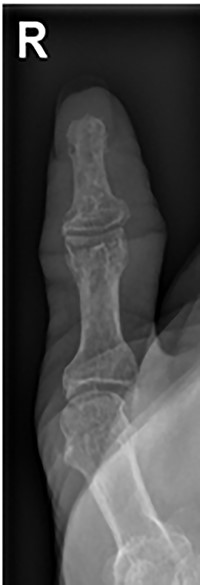

Her blood tests on presentation were unremarkable and X-rays of her right thumb showed a lytic lesion involving the tuft of the distal phalanx (Figs. 4 and 5). She was admitted to the hospital and was treated as having an infection of her right thumb with elevation and intravenous antibiotics. She underwent emergency surgery the next day for a washout and debridement of the right thumb. During the debridement in theatre, there was no pus in the pulp, but the bone was found to be eroded and soft, thus multiple specimens from the bone were sent for microscopy, culture and sensitivity, acid-fast bacilli (AFB) and histopathology.

AP radiograph of right thumb showing erosion of tip of distal phalanx.